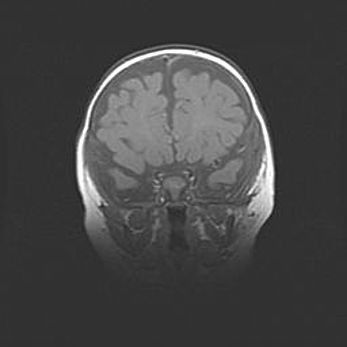

Наружная гидроцефалия с возможной атрофией височных областей.

Возраст: 28 дней

Вес: 3670 г

Пол: мужской

Окружность головы: 38 см

Срок гестации: 40 недель

Гидроцефалия головного мозга у новорожденных – это заболевание, которое характеризуется скоплением избыточного количества спинномозговой жидкости в желудочковой системе головного мозга в результате затруднения её перемещения от места выработки к месту поглощения в кровеносную систему или вследствие нарушения абсорбции. При открытой наружной форме гидроцефалии у новорожденных расширяются и переполняются субарахноидные пространства.

При нормотензивных  формах,  которые,  как  правило,  являются  следствием  перенесенных ишемических  повреждений  паренхимы  мозга,  возможно  сочетание микроцефалии  с нормотензивной гидроцефалией. В основе данных изменений лежит атрофия больших полушарий с преимущественной  локализацией  в  лобно-височных  областях.